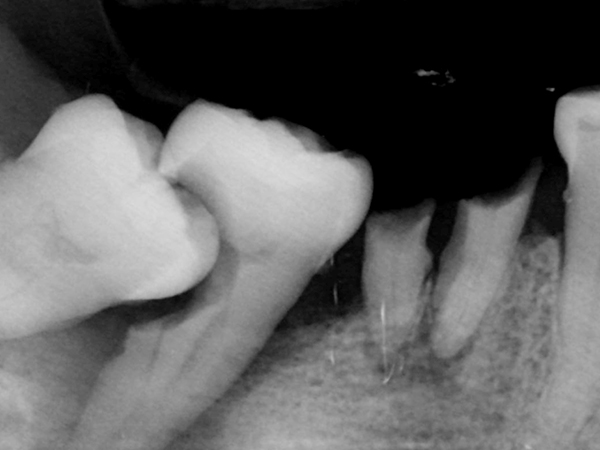

01. 검진 및 환자면담

정밀 검사를 통해

환자의 상태와 전신질환 등을

확인한 후에 수면 사랑니발치

여부 결정